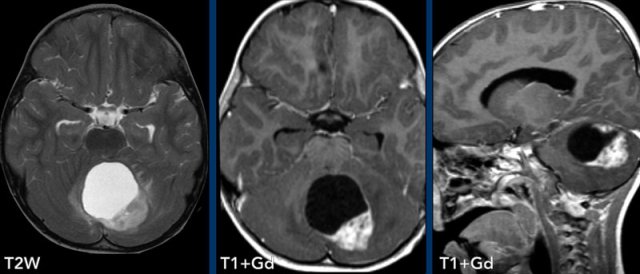

These images are of a 9-year old child who presented with headache.

Images

there is a large cystic posterior fossa mass with compression and

obstruction of the fourth ventricle and brainstem.

A solid contrast enhancing

nodule is present, as well as enhancement of the cyst wall.

Conclusion

Most likely diagnosis at this age is a pilocytic astrocytoma